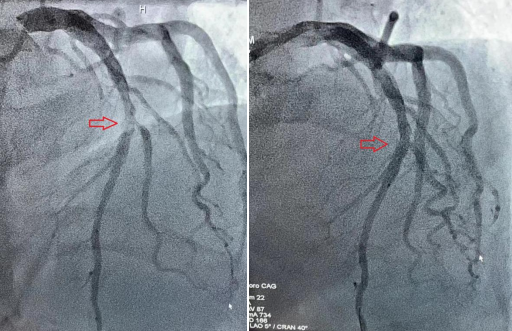

血管开通前 血管开通后

无独有偶,在雷先生刚刚下手术台不久,又一名50余岁的男性胸痛患者入院,急查心电图提示急性下壁心肌梗塞,李主任顾不上休息,带领介入团队再次上场。这次是患者血管被一个巨大的血栓堵死,在反复的血栓抽吸后,血管再次恢复了通畅。从患者进91porn 大门到血管开通仅仅用了不到一个小时,患者就被医护人员从死亡线上拉了回来,时间远远低于全国平均水平。